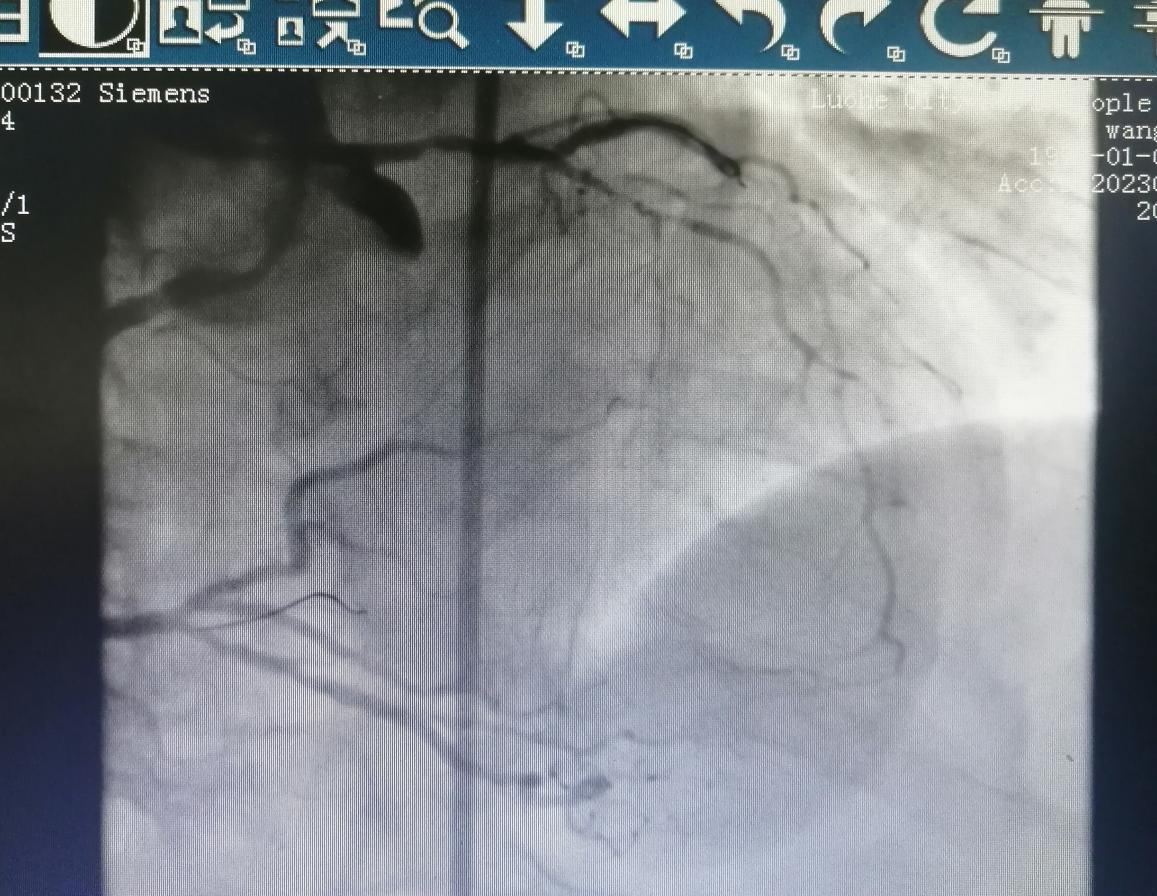

病例二

69歲的王阿姨,患有間斷性心前區(qū)不適2年。近日,因“心前區(qū)不適發(fā)作”入住心血管科。入院后,經(jīng)檢查冠脈造影發(fā)現(xiàn)前降支+回旋支閉塞病變。

金叔宣教授帶領(lǐng)心血管內(nèi)科介入團(tuán)隊(duì)為王阿姨制定了個(gè)體化的手術(shù)治療方案,即行右冠狀動脈造影+正向CTO,順利開通閉塞血管。

術(shù)后,王阿姨心前區(qū)不適癥狀較前明顯緩解。

術(shù)后: